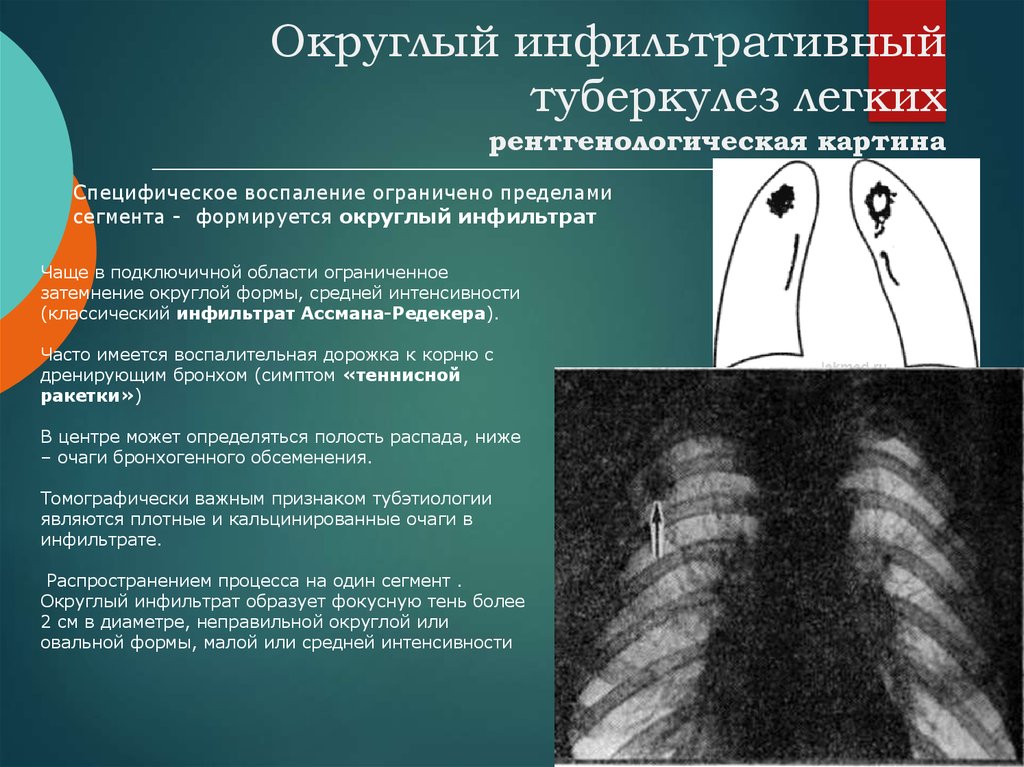

Очаговый и инфильтративный туберкулез презентация - 94 фото